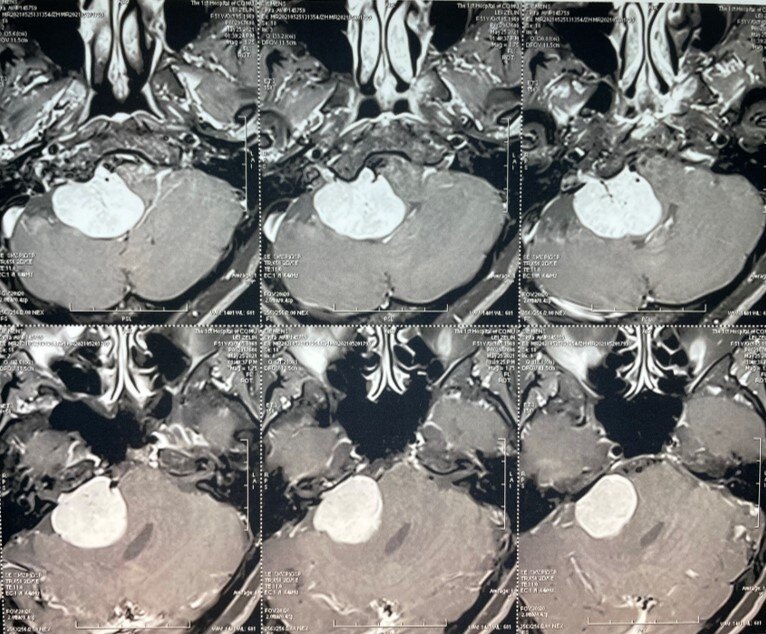

聲音嘶啞的罕見原兇:顱底腫瘤伴迷走神經(jīng)受壓

前幾日上午剛完成一臺手術(shù),就有護(hù)士趕來告訴我,有門診患者已等候半個多小時了。?剛到診室門口,就看到椅子上坐著一對老年夫妻。他們一進(jìn)診室就告訴我,自打年前被您診斷為顱底(右側(cè)巖錐、枕骨、斜坡處)惡性腫瘤后,就先后去了上海、北京找到了各大專家,甚至還請梅奧診所會診,專家們都同意這個診斷,但是無法進(jìn)行手術(shù)治療。最后幾經(jīng)波折,在中國醫(yī)科院腫瘤醫(yī)院廊坊質(zhì)子中心行質(zhì)子治療。雖然價格昂貴(1萬/次),但每次治療只需20分鐘,并且沒有不適的感覺。經(jīng)過33次質(zhì)子治療,在2月份療程結(jié)束了。中國醫(yī)科院腫瘤醫(yī)院的專家說,三個月后,你還是去當(dāng)初幫你診斷的杭州市一醫(yī)院復(fù)查一下。?在交流過程中發(fā)現(xiàn),老爺子聲音嘶啞的情況已經(jīng)較之前有明顯好轉(zhuǎn)。經(jīng)復(fù)查MRI檢查顯示,病灶大部分活性已經(jīng)消失,局部少許殘留(p1-3治療前,p4-6治療后),鄰近腦實質(zhì)、骨質(zhì)均未見明顯異常。看來,對于困難部位的疾病,質(zhì)子治療還是非常精準(zhǔn)有效的。病例提示:顱底病變,因為其位于顱頸交界區(qū)的特殊位置,影像檢查時容易被遺漏,也因此容易被臨床漏診、誤診。所以,對于患者表現(xiàn)為較典型顱神經(jīng)癥狀和體征的患者,臨床診斷,特別是影像診斷時,需要特別關(guān)注顱底結(jié)構(gòu)有無異常,盡早發(fā)現(xiàn)早期病變。???